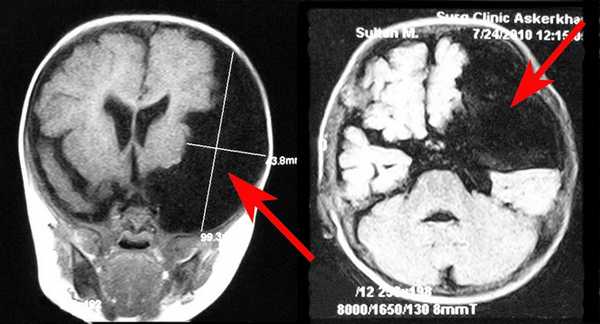

- МРТ головного мозга. Магнитно-резонансная томография — «золотой стандарт» диагностики внутричерепных новообразований. Ее проводят с контрастированием, поскольку киста не накапливает красящее вещество, в отличие от злокачественной опухоли. Для лучшей визуализации содержимого полости используют КТ головного мозга.

Оптимальным диагностическим методом для распознавания арахноидальных кист выступает МРТ головного мозга с контрастированием. Использование контрастных веществ позволяет отдифференцировать кисту от опухоли головного мозга. Основным критерием арахноидальной кисты, отличающим ее от опухоли, является отсутствие способности накапливать контраст. При помощи МРТ проводится дифференциальная диагностика с субдуральной гематомой, субарахноидальным кровоизлиянием, субдуральной гигромой, абсцессом, инсультом, энцефалитом и др. церебральными заболеваниями.

На сегодняшний день наиболее точным методом диагностики, позволяющим с высокой степенью точности отличить арахноидальную кисту от опухоли или гематомы, являются компьютерная томография (КТ) и магнито-резонансная томография (МРТ).

МРТ диагностика при арахноидальной кисте

Несмотря на то, что КТ позволяет точно определить размеры и расположение кисты, наиболее точную и полную информацию об образовании дает МРТ. Обычно для диагностики арахноидальной кисты проводится МРТ-сканирование с введением в кровоток пациента контраста. При этом опухоли мозга имеют свойство накапливать контраст, а кисты не впитывают его из кровеносных сосудов, что очень четко видно на МРТ.

Также МРТ-сканирование позволяет отличить кисту от кровоизлияний, гематом, гигром, абсцессов и других заболеваний со сходной симптоматикой. Кроме того, МРТ дает возможность выявить кисту даже в тех случаях, когда у пациента еще нет никаких проявлений, а сама киста имеет размеры всего в несколько миллиметров.